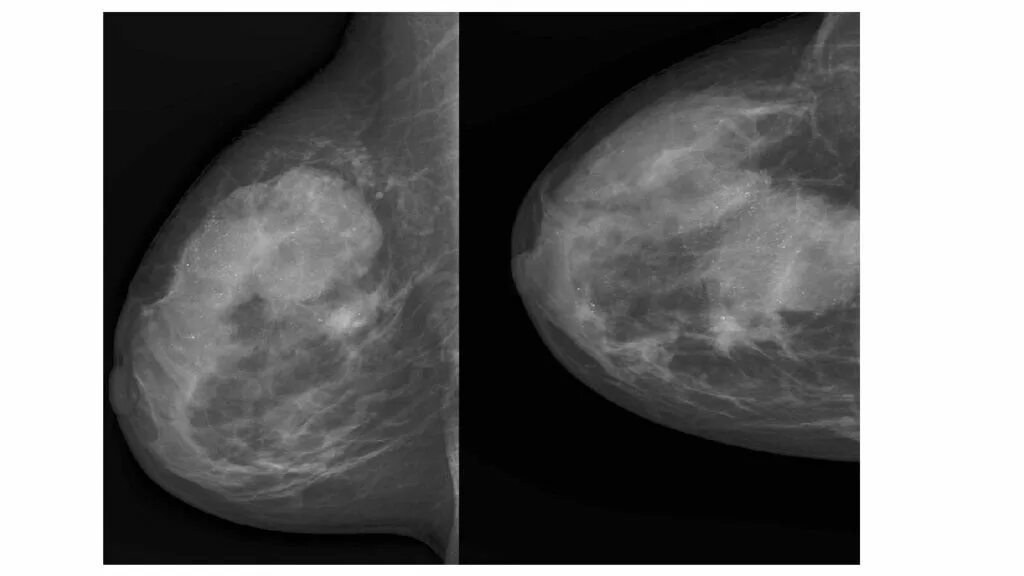

Доброкачественное новообразование молочной железы